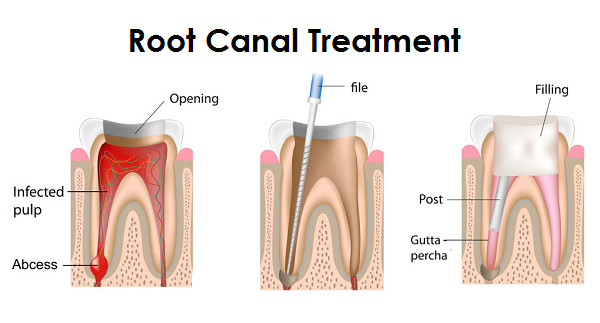

A root canal treatment, also known as endodontic therapy, is a procedure aimed at treating infection or inflammation within the tooth's pulp. This treatment is essential for saving a tooth that might otherwise need to be extracted.

1. Diagnosis and X-ray: Your dentist will examine the affected tooth and take an X-ray to assess the extent of the infection.

2. Anesthesia: Local anesthesia is administered to numb the tooth and surrounding area, ensuring a painless experience.

3. Pulp Removal: The infected or damaged pulp is carefully removed from the tooth.

4. Cleaning and Disinfection: The interior of the tooth is thoroughly cleaned and disinfected to remove all bacteria.

5. Filling: The cleaned root canals are filled with a biocompatible material and sealed to prevent further infection.

6. Restoration: A crown is usually placed on the treated tooth to restore its function and appearance.